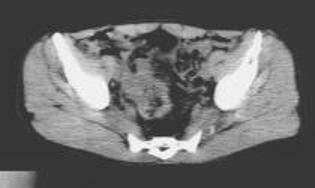

病历摘要:男,54岁病史:间歇性肉眼血尿伴下腹部隐痛7月余。为全程血尿,浓茶色,并有尿频尿急尿痛。当地医院曾造影检查示“膀胱结石”,入院前3天当地医院检查示“膀胱肿瘤”体查:心肺腹无明显阳性体征,双肾区无叩痛,双输尿管行程无压痛点,膀胱区未见肿胀、隆起实验室检查:尿常规:淡黄色,混浊,潜血大量,镜检白细胞370/μl(↑)